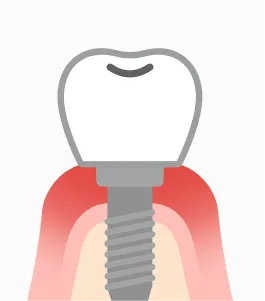

インプラント周囲炎

インプラントのリスクで最も注意すべきものが、歯周病菌への感染によって起こる「インプラント周囲炎」です。自覚症状がないまま進行し、最終的にインプラントを支える骨を溶かしてしまうことが、インプラントの寿命を縮める最大の原因です。

- 1 初期

インプラント周りの歯茎が腫れる、出血する。この段階なら適切なケアで改善可能。